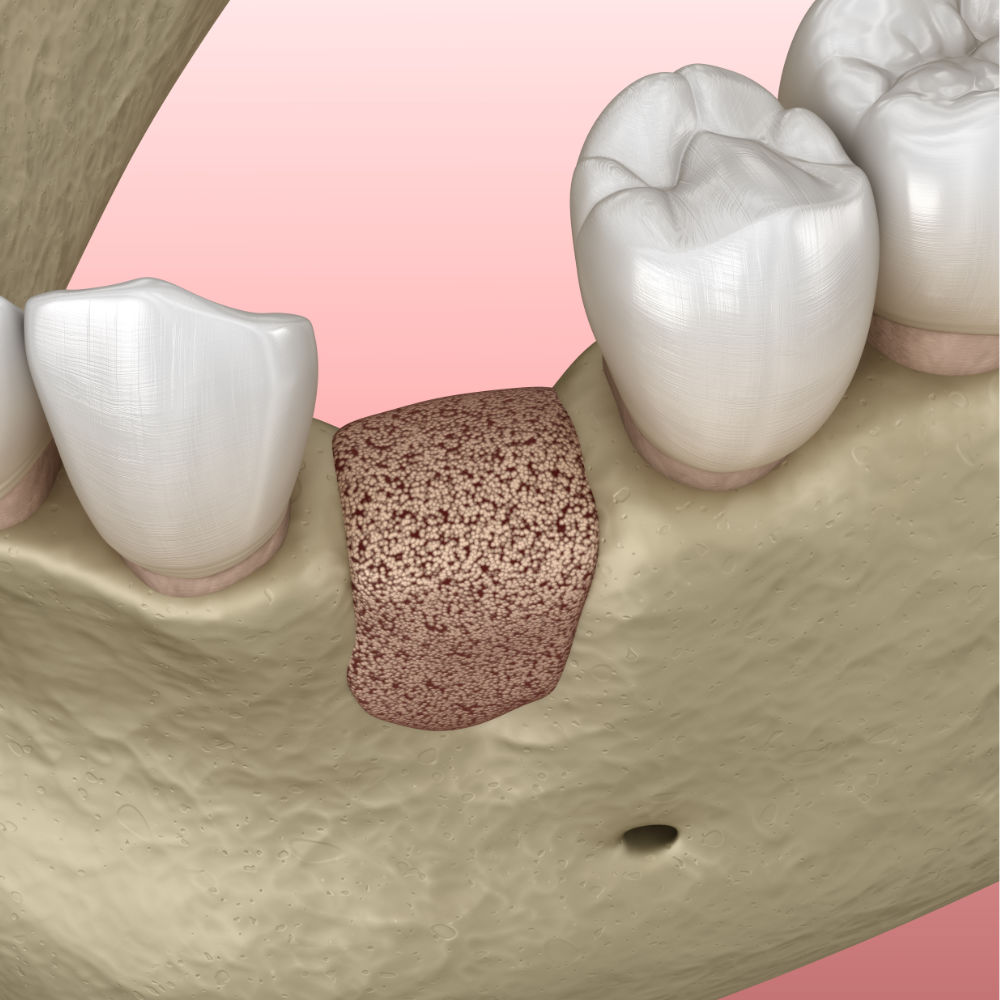

En effet, une reconstruction osseuse (Greffe osseuse) est indispensable, pour rétablir la hauteur ou la largeur de l’os maxillaire, avant ou en même temps que l’implantation. Ce sont soit les os du patient ou un substitut osseux qui sont utilisés comme matériau de comblement.